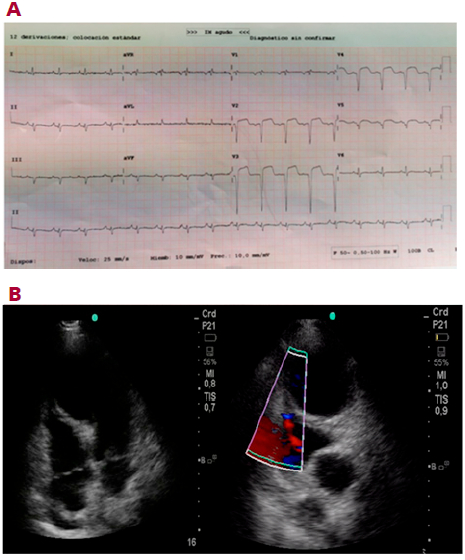

En la valoración inicial la paciente se encuentra con aceptable estado general, con cifras de TA de 100/60mmHg, eupneica en reposo; satura 98% sin aporte de oxígeno suplementario. Se realiza ECG donde se objetiva ritmo sinusal a 110 lpm con QS en V1-V4 y elevación del segmento ST en V2-V5. En el ecocardiograma se objetiva una imagen de CIV restrictiva a nivel septal, con identificación clara del shunt, una zona aneurismática anteroseptoapical y aquinesia que se extiende hasta el septum medio. La FEVI (fracción de eyección ventricular izquierda) globalmente estimada es 40%. (Figura 1 A y B)